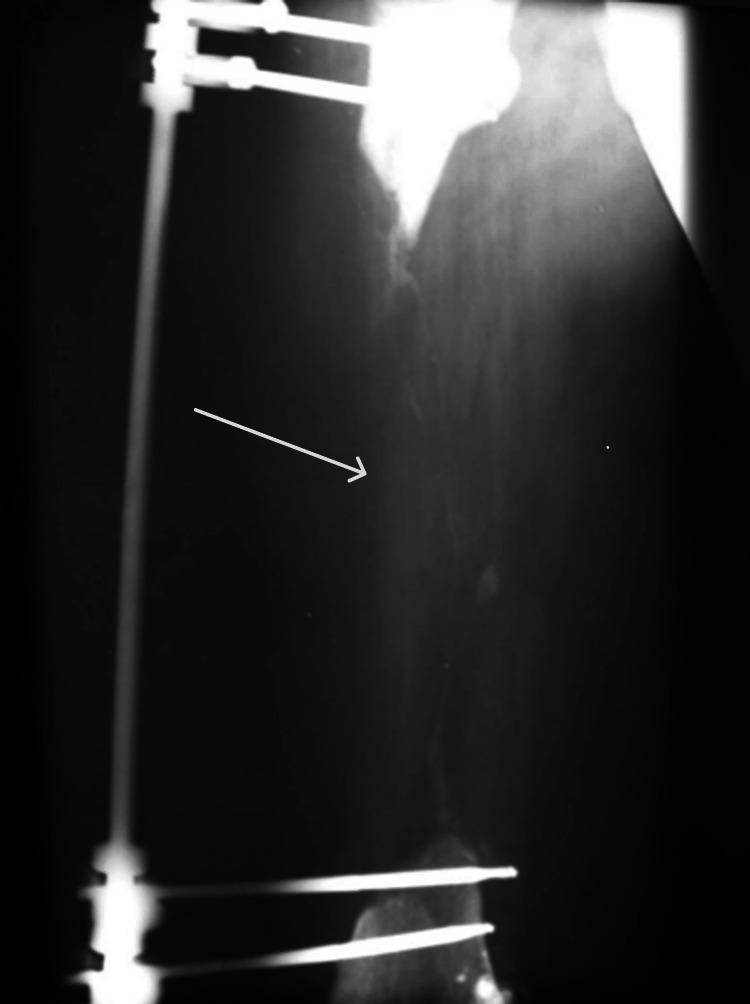

The vascularized fibula flap is often utilized in various reconstructive surgeries to cover a bone or soft tissue defect due to its generous length, adequate vascularization, and the possibility of removal with minimal loss of limb function. We present a 32-year-old male patient with a 27-cm femoral diaphysis defect caused by a high-impact car accident, which led to multiple femoral fractures and was further complicated by osteomyelitis. Initial consultations with other physicians advised limb amputation as the sole approach due to the severity of the case and potential complications. Upon presentation at Kuzanov Clinic, the possibility of salvaging the limb using the vascularized fibula flap was proposed. A 27-cm fibula flap was harvested and transplanted to the femoral defect. Anastomosis was established between the vasculature of the flap and the recipient zone. A few months after the surgery, an upper fibular fracture occurred, which later healed, and the fibula hypertrophied. At a 10-year follow-up, the patient remains ambulatory, with limb shortening effectively managed with a custom shoe.

带血管蒂腓骨瓣因其长度足够、血供充足且切除后对肢体功能影响最小,常被用于各种重建手术中以覆盖骨或软组织缺损。我们报告一名32岁男性患者,因高冲击力车祸导致股骨干27厘米缺损,引发多处股骨骨折,并伴有骨髓炎。由于病情严重及潜在并发症,最初咨询其他医生时建议截肢作为唯一治疗方法。患者到库扎诺夫诊所就诊时,提出了使用带血管蒂腓骨瓣挽救肢体的可能性。切取了一段27厘米的腓骨瓣并移植到股骨缺损处。在瓣的血管与受区之间建立了吻合。术后几个月,腓骨上段发生骨折,随后愈合,腓骨出现肥大。在10年随访时,患者仍可行走,通过定制鞋有效解决了肢体短缩问题。